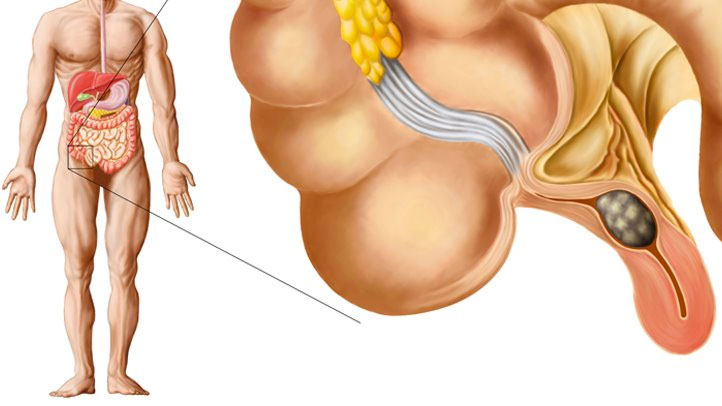

Cari Tahu Letak Dan Penyebab Usus Buntu

Cari Tahu Letak Dan Penyebab Usus Buntu